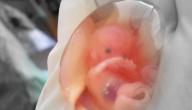

يُطلق على عمليّة إنهاء الحمل مُبكّراً، أي خلال الثّلث الأوّل من الحمل في الغالب، الإجهاض (بالإنجليزيّة: Abortion)، وتتمّ عمليّة الإجهاض تحت الإشراف والتّطبيق الطبيّ المُتخصّص في المستشفى، أو المركز الطبيّ، أو العيادة الطبيّة، بينما يُطلق على انتهاء الحمل من تلقاء نفسه بسقوط الجنين (بالإنجليزيّة: Miscarriage) أو الإجهاض التلقائيّ (بالإنجليزيّة: Spontaneous Abortion).[١] وهناك طريقتان رئيسيّتان للإجهاض؛ الإجهاض باستخدام الأدوية ويُسمّى الإجهاض الطبيّ أو الدوائيّ (بالإنجليزيّة: Medical Abortion)، والإجهاض بالعمليّات الجراحيّة ويُسمّى الإجهاض الجراحي (بالإنجليزيّة: Surgical Abortion)،[١] ويعتمد اختيار طريقة الإجهاض على الإمكانيّات المُتاحة، ومدّة الحمل، ورغبة الحامل، ومن الجدير بالذّكر أنّ الإجهاض الدوائي لا يمكن اللجوء إليه إذا كان عمر الحمل أكثر من عشرة أسابيع.[٢]

- ميفيبريستون (بالإنجليزيّة: Mifepristone): يُعارض هذا الدّواء قدرة الجسم على الاستفادة والانتفاع من هرمون الحمل الأساسيّ البروجسترون (بالإنجليزيّة: Progesterone)، والذي يُساعد في تحضير الرّحم لاستقبال المُضغة (بالإنجليزيّة: Embryo) وانغراسها (بالإنجليزيّة: Implantation)، حيث يقوم الجسم بطرح المُضغة الجنينيّة من خلال انقباضات عضليّة متلاحقة في حال لم تتوفّر الكميّة الكافية من البروجسترون لانغراس المُضغة في بطانة الرّحم، وتجدر الإشارة إلى أنّ نسبة نجاح الإجهاض باستخدام هذا الدّواء وحده لا تتجاوز الثّمانين بالمئة.